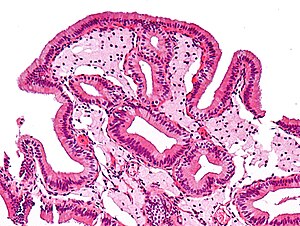

Gallbladder cholesterolosis. H&E stain. | |

| LM | abundant foamy macrophages in the lamina propria, +/-papillary hyperplasia |

| LM DDx | cholesterol polyp of gallbladder |

- Numerous foamy macrophages in the lamina propria.

- +/-Papillary hyperplasia.[2]

- Cholesterol polyp of gallbladder - polypoid shape.